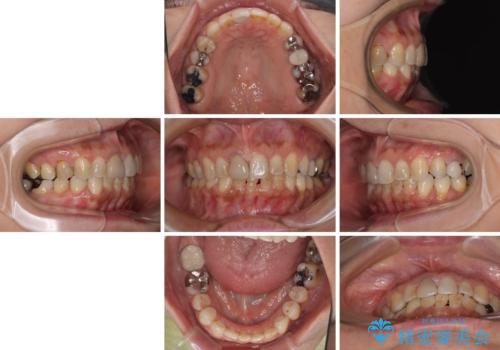

痛みがなくなり歯列が整ったことで、残っている銀歯も気になり始めているようです。

マウスピース生活に疲れてしまったとのことで、暫くお休みをしてから銀歯の治療を再開していく予定です。